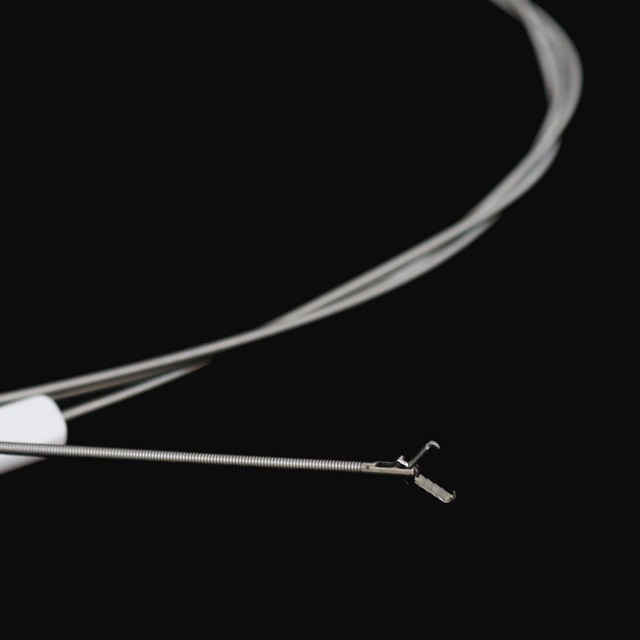

● Icipe ca ku nse, ica kubomfiwa fye na{000)}

Umusango wa Jaw

FG{0{0}}K-A1 |

FG{0{0}}K-A3 |

FG{0{0}}K-A4 |

FG{0{0}}K-A5 |

FG{0{0}}K-A7 |

FG{0{0}}K-A8 |